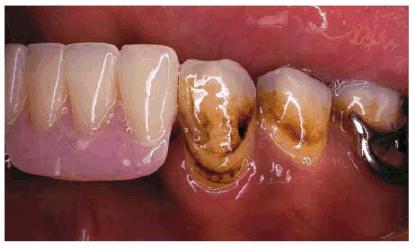

Figure 16-2A and B: Total neglect resulted in severe staining

of this patient's teeth.